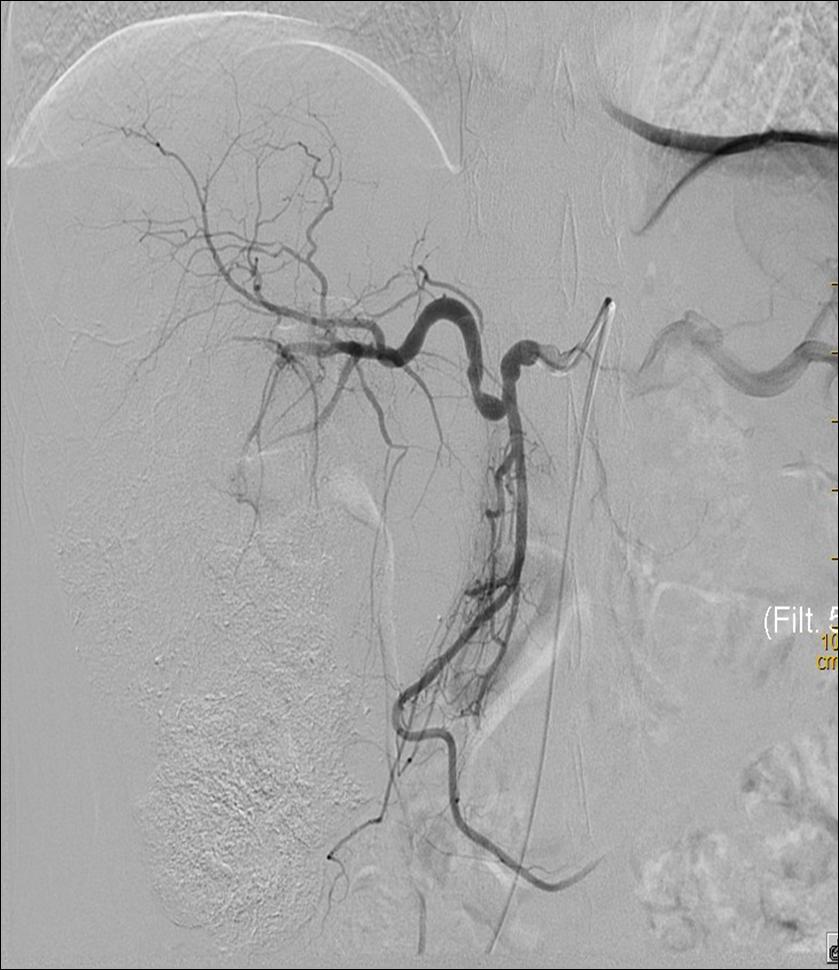

肝胆内科开展肝脏恶性肿瘤介入手术(包括经肝动脉灌注化疗栓塞术、经肝动脉置管持续化疗灌注术)、经皮经肝胆道穿刺引流术(PTCD术)、经皮经肝胆道置管术、经颈静脉肝内门体分流术(TIPS术)、胃冠状静脉栓塞术、部份脾动脉栓塞术(PSE)、肝脏穿刺活检术。

TIPS术前 TIPS术后

原发性肝癌TACE术前 原发性肝癌TACE术后